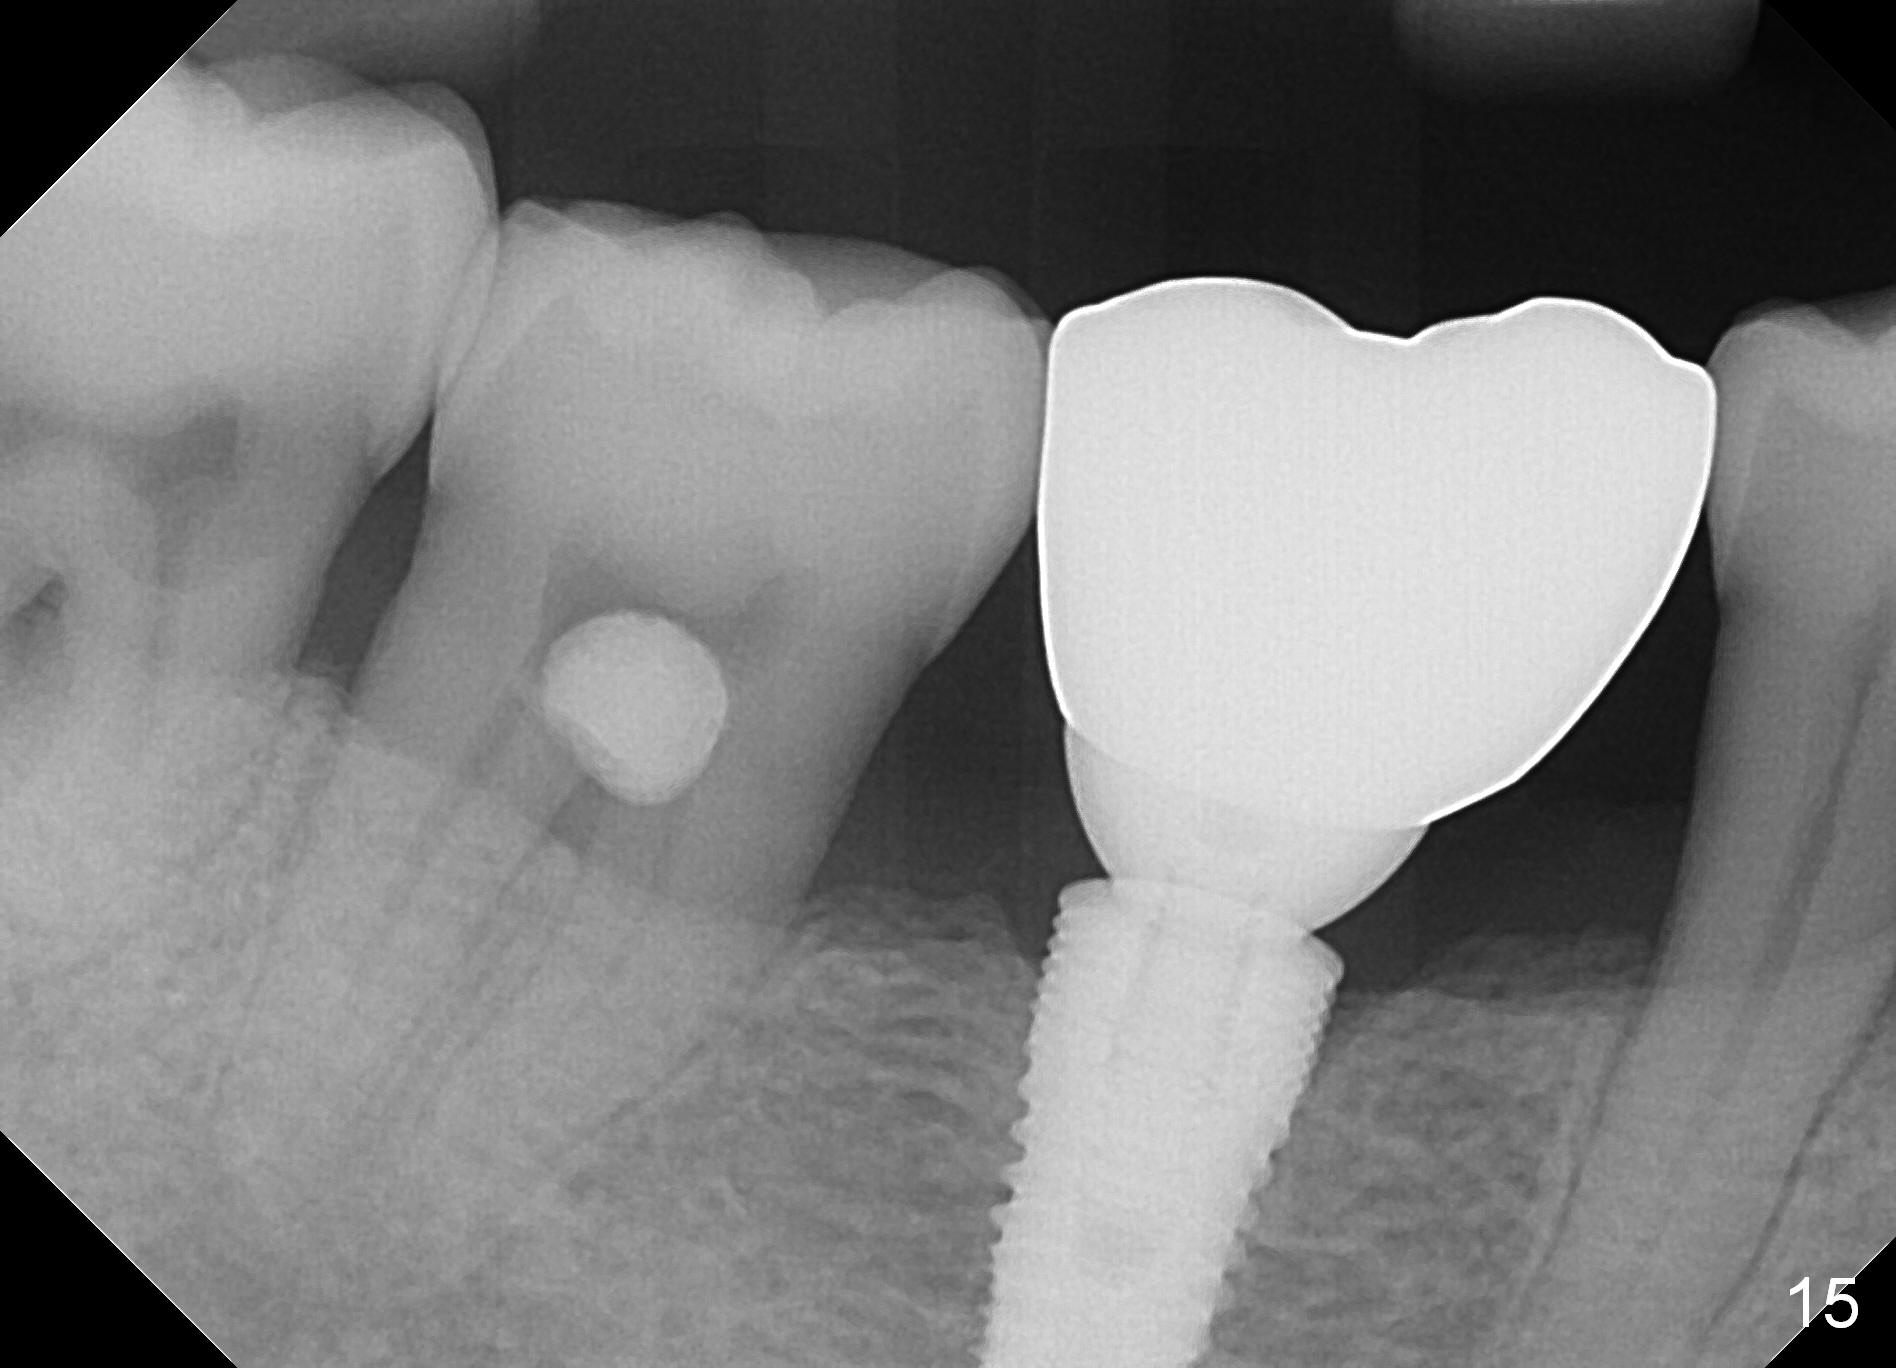

The patient returns for recall 9 months post cementation. His concern is inability to masticate hard on the right side. The tooth #29 has mobility I with bone loss (Fig.14 ^). Six months later, the symptom disappears. In fact occlusal equilibrium should be provided. There is no bone loss 2 years 2 months post cementation (Fig.15).